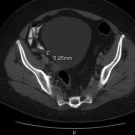

An 18-year-old man presented with a 3-day history of fever, sore throat, and neck swelling. His past health was unremarkable, and his immunizations were up to date. There was no history of travel outside...